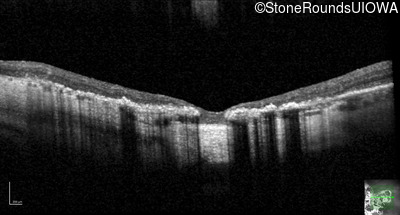

Optical Coherence Tomography - Left - 10/140

Exemplar / OCT Stack